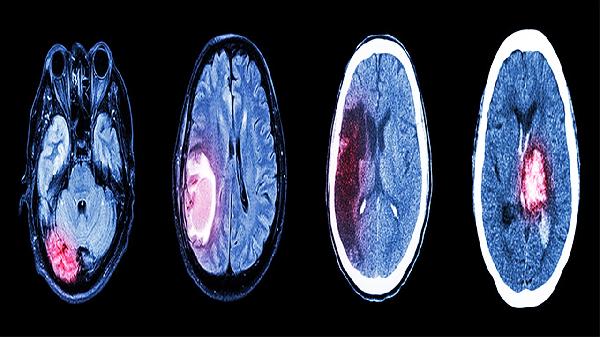

婴儿颅内出血的症状表现主要包括意识状态改变、异常哭闹、喂养困难、肌张力异常及惊厥发作。颅内出血的临床表现与出血部位、出血量及婴儿月龄密切相关,需结合神经系统检查及影像学结果综合判断。

可表现为肢体过度松软或强直,下肢肌张力增高需排除早产儿脑室周围白质软化。局灶性肌力下降可能提示脑实质出血,需进行磁共振弥散加权成像确诊。